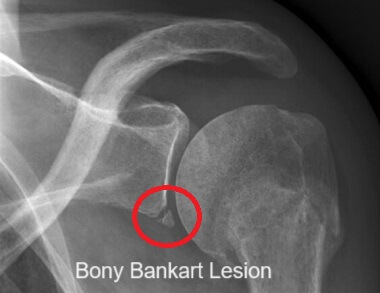

A Bankart lesion, aka glenoid labrum tear, is where there is damage to the special layer of cartilage lining the shoulder joint.

A Bankart lesion is when there is damage to the lower portion of the glenoid labrum, causing it to tear away from the bony socket.

Bankart lesions are typically caused by an anterior dislocation of the shoulder, where the head of the humerus is forced forwards and pops out of the glenoid socket. As the bone is forced forwards, it can damage the labrum, causing it to tear.